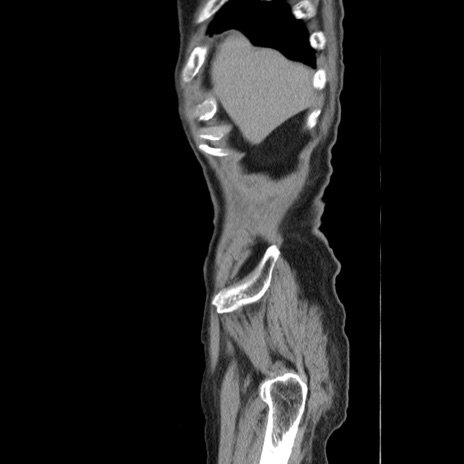

症例24(矢状断像)

冠状断像